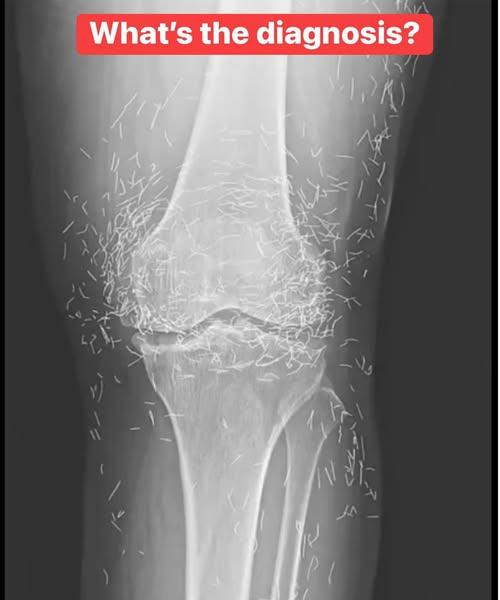

When a 65-year-old woman went in for an X-ray to uncover the cause of her unrelenting knee pain, doctors expected to see signs of arthritis. What they found instead left them stunned: hundreds of tiny gold acupuncture needles embedded deep inside her tissue — a hidden legacy from years of alternative treatment.

When radiologists reviewed the woman’s X-ray, they couldn’t believe their eyes. Her knees were peppered with countless specks of metallic glimmer — hundreds of gold acupuncture needles, permanently lodged under her skin.

Unlike typical acupuncture sessions, where thin needles are temporarily inserted and then removed after a short time, this particular technique left the needles in place indefinitely. The needles, believed to be made of sterile gold, were meant to provide “ongoing stimulation” to relieve pain and improve joint function.

This type of gold thread acupuncture is still practiced in some Asian countries as a treatment for osteoarthritis and other joint conditions, particularly in older patients who may not tolerate medications well. The idea behind it is simple but controversial: implant gold threads around painful joints to continuously stimulate healing energy.